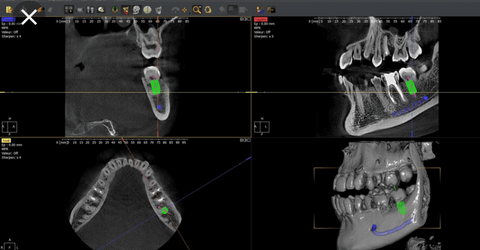

Imagen dental 3d

Hemos incorporado en nuestra clínica dental de San Agustín del Guadalix, el servicio de radiología dental 3d, con el escaner dental de haz cónico Owandy I-max 3d.

El TAC escaner dental es la forma abreviada de designar la Tomografía Computerizada de Haz Cónico (CBCT en inglés), una técnica radiográfica que utiliza rayos X para obtener imágenes de cortes o secciones con las que construir una imagen tridimensional de las estructuras dentomaxilares (dientes, maxilares y mandíbula).

Las imágenes tridimensionales que se obtienen permiten observar cualquier estructura de la boca, diagnosticar de forma más precisa y planificar los tratamientos.